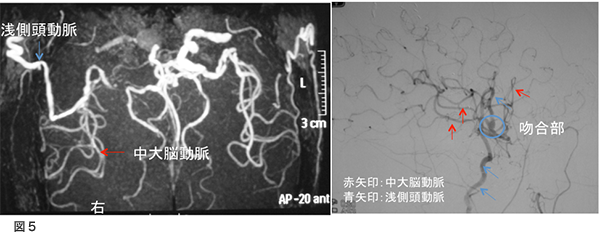

術後MRA、脳血管造影 図5

右は術後のMRAですが、術前ほとんど写っていなかった右中大脳動脈がバイパスからの血流で描出されるようになっています。左は、脳血管造影(右外頸動脈撮影)ですが、浅側頭動脈から中大脳動脈全域が描出されています。